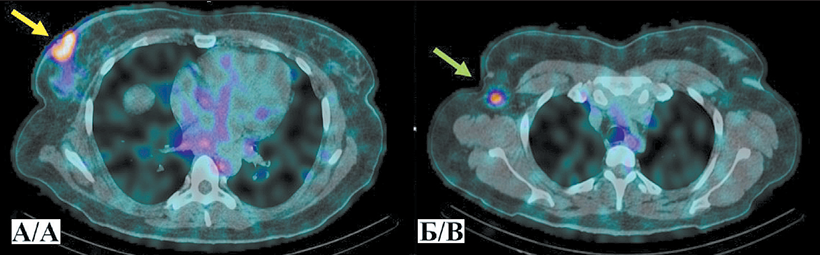

Клинический случай № 1. Пациентка К., 51 год, диагноз: Рак правой молочной железы, IIIC стадия (T2N3M0), мультицентричный рост, метастатическое поражение аксиллярных и подключичных лимфоузлов. ОФЭКТ/КТ выполнена через 2 ч после внутривенного введения РФЛП [99mTc]Tc-DB8 в дозировке протеина 80 мкг. По результатам исследования помимо первичной опухоли и метастатических лимфоузлов выявлен высокий уровень аккумуляции препарата [99mTc]Tc-DB8 в проекции V ребра справа по средней аксиллярной линии. Повторный анализ компьютерных томограмм органов грудной клетки (КТ ОГК) подтвердил наличие очага литической деструкции, расцененного как возможный метастаз и взятого под наблюдение. При КТ ОГК в динамике в указанной проекции визуализировался участок неравномерных склеротических изменений, что интерпретировано как ответ на терапию.

1. Рис. 1. ОФЭКТ/КТ органов грудной клетки больной К. через 2 ч после инъекции [99mTc]Tc-DB8 в дозировке протеина 80 мкг: А – желтая стрелка указывает на первичную опухоль, красная стрелка – на участок гиперфиксации РФЛП в проекции V ребра по средней аксиллярной линии справа; Б – зеленая стрелка указывает на метастатический аксиллярный лимфоузел. Примечание: рисунок выполнен авторами